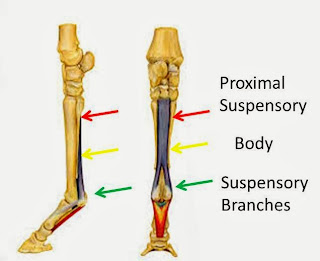

The leg feels full and soft to the touch, with some warmness inside. No cuts or surface wounds. She'll lift it for me happily but doesn't love me pressing on it. Swelling is much reduced after wrapping but returns if wraps stay off. She is mostly standing square, occasionally rests it, and seems "normal" other than having a very puffy leg. She's on box rest now except a few steps out for hosing, but does not seem terribly uncomfortable on those steps. I have no experience with ligament or tendon injuries, but am fearing either suspensory branch or deep digital flexor. I have always been very careful with my horses and have also been very lucky/blessed (!) not to have had any soft tissue injuries before... so I don't have enough experience to know what I'm looking at. Does anyone here have any other possible guesses, since I'm fairly certain to be torturing myself until she's seen? I've read all about the path back from these tendon and ligament injuries, so I'm aware of all that and will cross that bridge Monday. Luckily we have a great vet...

The leg feels full and soft to the touch, with some warmness inside. No cuts or surface wounds. She'll lift it for me happily but doesn't love me pressing on it. Swelling is much reduced after wrapping but returns if wraps stay off. She is mostly standing square, occasionally rests it, and seems "normal" other than having a very puffy leg. She's on box rest now except a few steps out for hosing, but does not seem terribly uncomfortable on those steps. I have no experience with ligament or tendon injuries, but am fearing either suspensory branch or deep digital flexor. I have always been very careful with my horses and have also been very lucky/blessed (!) not to have had any soft tissue injuries before... so I don't have enough experience to know what I'm looking at. Does anyone here have any other possible guesses, since I'm fairly certain to be torturing myself until she's seen? I've read all about the path back from these tendon and ligament injuries, so I'm aware of all that and will cross that bridge Monday. Luckily we have a great vet...